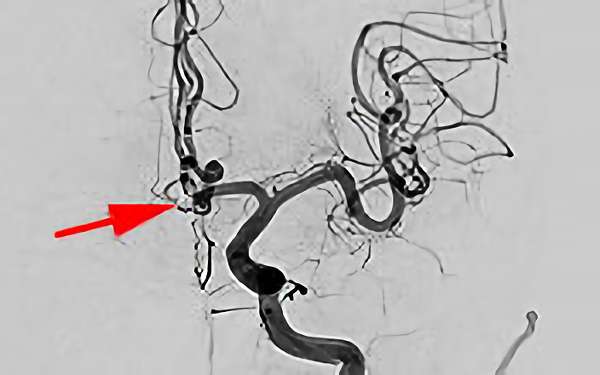

No.1617 手術前